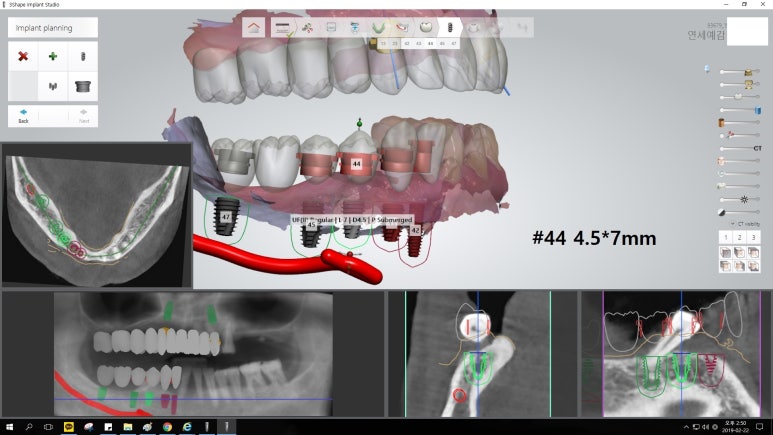

오늘은 임플란트, 조금 더 안아프고 간편하게 할 수 있는 방법에 대해

실제 저희 치과에서 진행한 사례를 통해 알아보고자 합니다.

50대의 나이에도 남은 이가 거의 없는 분입니다.

이러한 세세한 시뮬레이션, ct를 이용한 컴퓨터 분석을 통해

더 정확하고 안전하게 적절한 위치에 임플란트를 식립할 수 있었으며

절개가 없는 비절개 방식을 이용한 인플란트로

수술시간이 짧고 실밥을 풀 필요가 없으며, 환자분의 만족도도 높습니다.